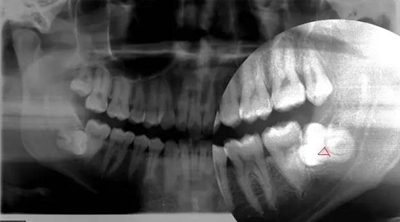

因正畸需要拔除智齒

3.jpg